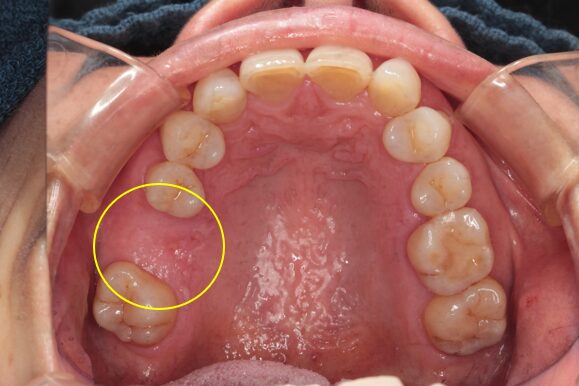

48歳女性